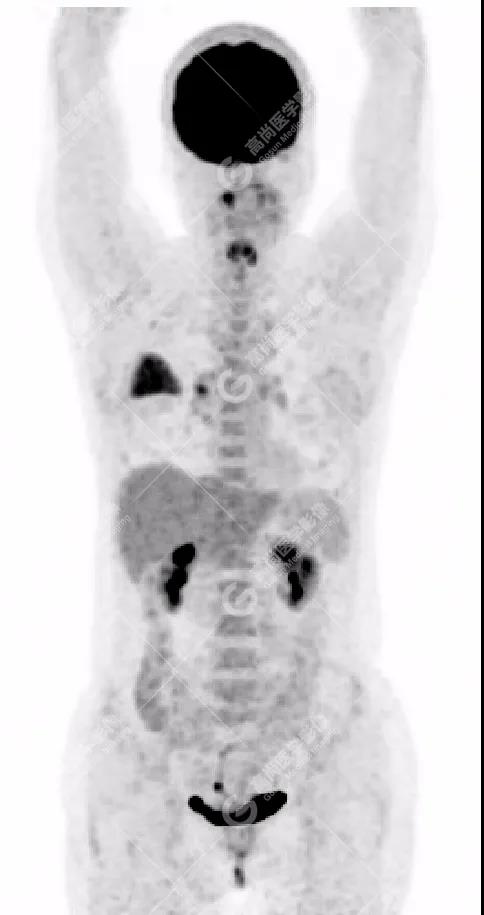

PET/CT影像圖

右肺上葉斑片狀高密度影,部分實(shí)變,邊界清楚,未跨葉間裂;內(nèi)空氣支氣管征、蟲(chóng)蝕樣空洞、周?chē)鷷炚鳎环派湫詳z取增高,SUVmax=4.1。

右肺上葉后段胸膜下片塊狀高代謝病灶,考慮為肺淋巴瘤,請(qǐng)結(jié)合臨床病理。

18F-FDG PET/CT能夠顯示大多類(lèi)型的淋巴瘤,尤其是惡性程度較高的病理類(lèi)型,但對(duì)低度惡性淋巴瘤、尤其是MALT淋巴瘤的顯示能力尚存在爭(zhēng)議。非MALT類(lèi)型PPLSUV明顯高于MALT淋巴瘤,在一定程度上說(shuō)明惡性程度越高,病灶濃聚顯像劑的能力越強(qiáng)。除病理類(lèi)型外,PET顯示淋巴瘤還與腫瘤的部位和大小有關(guān)。肺為含氣臟器,放射性本底低,無(wú)生理性攝取干擾,即使病灶的放射性攝取較低,也能產(chǎn)生足夠?qū)Ρ榷?。肺部MALT淋巴瘤往往因惡性程度較低、病程較長(zhǎng)而發(fā)展成較大病灶,足以攝取較多顯像劑,產(chǎn)生放射性濃聚。此外, PET/CT檢查能夠覆蓋全身,并敏感地顯示全身其它部位有無(wú)病灶,有助于鑒別PPL和繼發(fā)性肺部淋巴瘤。值得注意的是,18F-FDG PET/CT 顯像為非特異性顯像,肺部其他病變(如肺癌、炎癥、結(jié)核等)也可產(chǎn)生放射性濃聚影,僅憑PET圖像往往無(wú)法進(jìn)行準(zhǔn)確鑒別,需密切結(jié)合PET/CT中的CT影像特征及相關(guān)臨床資料,以減少誤診【3】。盡管PPL發(fā)病率低,臨床表現(xiàn)缺乏特異性,但18F-FDG PET/CT表現(xiàn)具有一定特征:1.雙肺多發(fā)、多種形態(tài)病灶,右肺中葉受累常見(jiàn);2.較大腫塊或?qū)嵶儾≡羁缛~分布,內(nèi)有充氣支氣管征;3.大多數(shù)病灶FDG放射性攝取增高。當(dāng)肺部病變具備上述影像表現(xiàn)、而臨床治療效果欠佳時(shí),應(yīng)想到PPL,尤其MALT淋巴瘤的可能性,盡早穿刺活檢,以獲得病理學(xué)診斷【3】。